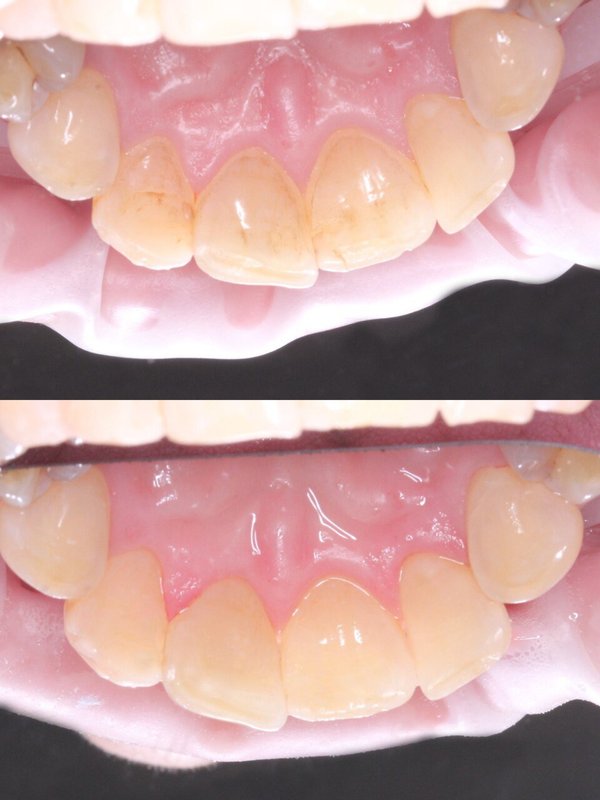

Фотогалерея

Если вы собираетесь добиться сияющей улыбки, то работу над ней лучше доверить экспертам. В стоматологической клинике Династия Н имеется специализированное оборудование для того, чтобы ваши зубы снова стали белоснежными. В нашей стоматологии оказывают услуги лечения кариеса, удаления зубов, компьютерной томографии, отбеливания, исправления прикуса, рентгенологической диагностики, изготовления имплантов, а также установки металлокерамики, брекетов, имплантов, виниров. С нами ваша улыбка будет яркой, а зубы крепкими!